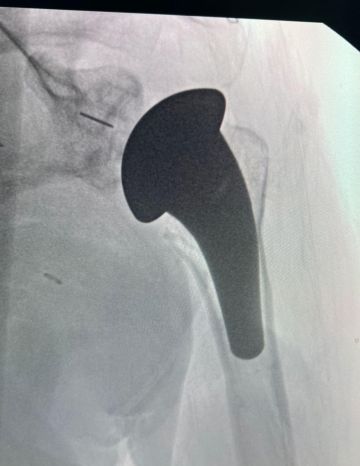

في إنجاز طبي جديد، نجح فريق وحدة الأطراف العلوية بقسم جراحة العظام في مدينة الملك سعود الطبية – عضو تجمع الرياض الصحي الأول – في إجراء أول عملية استبدال كامل لمفصل الكتف لمريضة كانت تعاني من احتكاك شديد في المفصل لأكثر من عامين، مما أثّر على قدرتها على الحركة وممارسة أعمالها اليومية.

وأوضح استشاري جراحة العظام والأطراف العلوية وقائد الفريق الطبي، الدكتور بندر السهلي، أنه تم إجراء الفحوصات والتحاليل اللازمة قبل العملية، بما في ذلك الأشعة السينية والمقطعية والرنين المغناطيسي وفحوصات القلب، لتقييم حالتها بدقة وتحديد نوع التدخل المناسب. وأضاف أن الفريق الطبي أجرى عملية استبدال مفصل الكتف بالكامل باستخدام تقنية متقدمة تُمكّن من تحسين الحركة وتقليل الألم بشكل كبير.

وأفاد الدكتور السهلي بأن العملية تكللت بالنجاح – ولله الحمد – وتمت متابعة المريضة بعد العملية من قبل الفريق الطبي وأخصائيي العلاج الطبيعي، مع وضع خطة تأهيل مخصصة لضمان استعادة الحركة تدريجيًا وتحسين جودة حياتها.